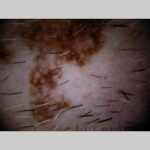

Melanoma-in-situ = الميلانوم من الدرجة صفر